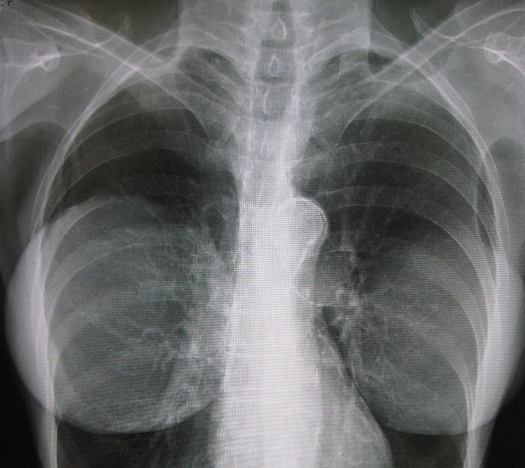

Trials in breast growth (and re-growth in the case of breast cancer survivors recovering from mastectomies, lumpectomies and quadrantectomies) have been promising. Since the tissues induce the formation of blood vessels, the regenerative cells link the blood supply to the fat cells they’re traveling with, presenting a much lower risk of reabsorption than the injection of fat cells alone. In 2007, a cosmetic surgeon in Japan began a human study and reported that patients injected with the stem-cell-loaded fat solution grew an average of 4 centimeters in breast circumference while the tissue remained soft and natural.